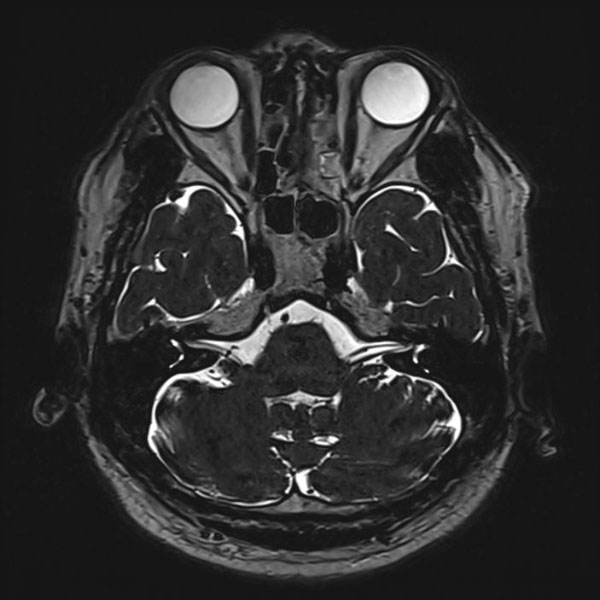

手術前

(MR1)